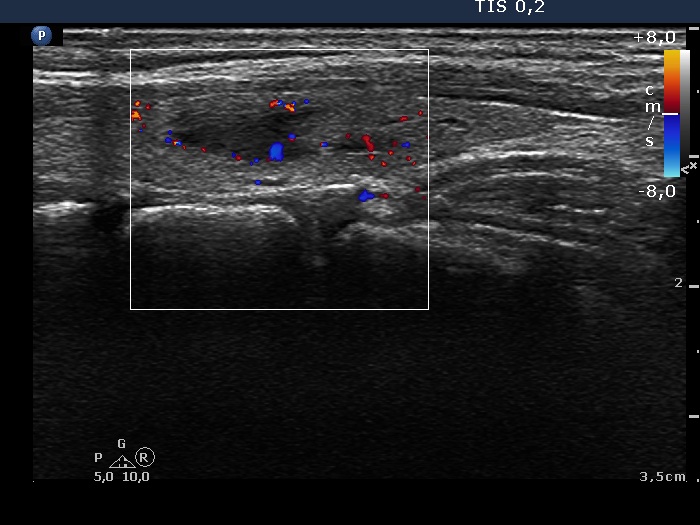

Left lobe, longitudinal scan, color Doppler mode. The nodule presents signs of perinodular flow.